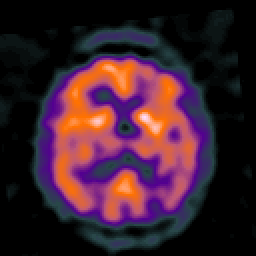

Alzheimer's disease: overlay -- Slice #31

[Home][Help][Clinical] Slice 31